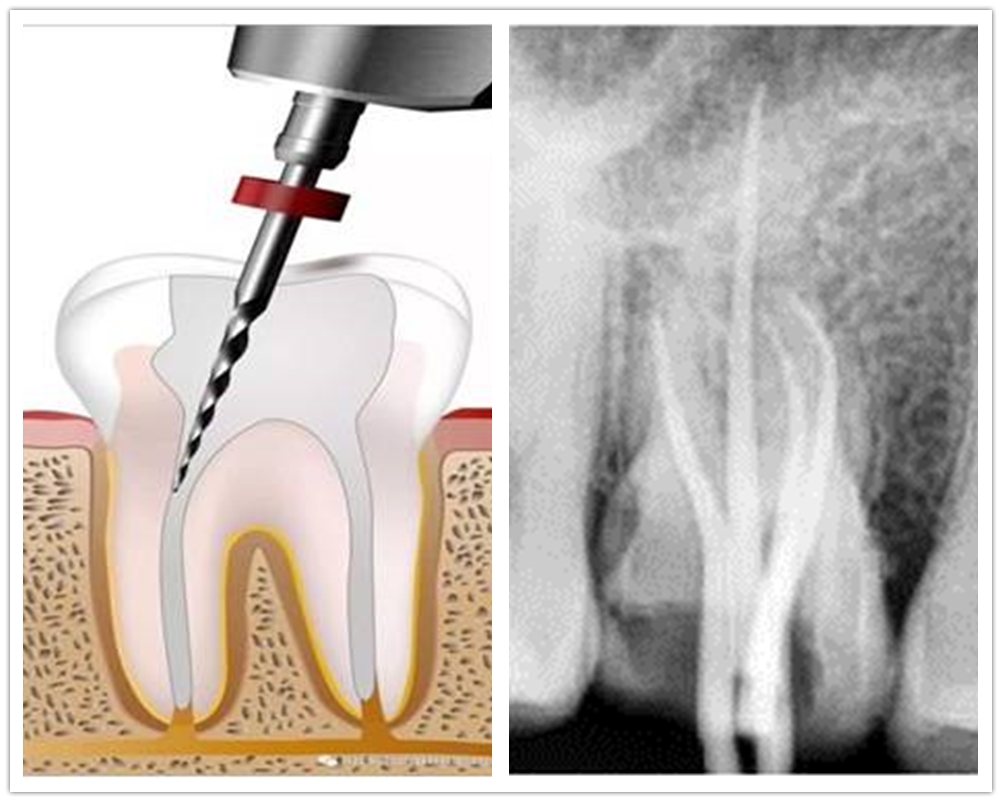

一、口腔内科方面:常规开展牙体牙髓病、牙周病、粘膜病、儿童牙病的治疗及光固化美容修复、牙周病手术治疗及牙周病松动牙固定术等。近年来新开展了热牙胶垂直加压充填技术,使根管治疗工作更加规范,极大地提高了患牙保存率。进一步加强了老年牙病和儿童牙病的治疗工作。将口腔新技术、新理念、新材料应用于临床工作中,同时做好牙病宣教工作,使广大口腔疾病患者得到更加规范和人性化的服务。